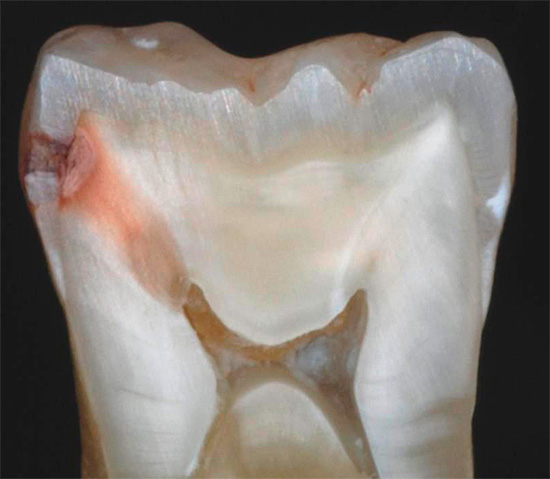

Tuttavia, se si osserva lo stadio del danno allo smalto nelle prime fasi, si verifica un processo già irreversibile: la carie della dentina. In questa fase, i componenti minerali vengono già lavati dalla dentina stessa, che, come ricorderete, è la base del dente.

La dentina è significativamente diversa nella sua composizione chimica e struttura dallo smalto dei denti. È molto meno resistente e contiene il 20% di composti organici. Lo spessore della dentina nel dente raggiunge una media da 2 a 6 mm. Allo stesso tempo, la dentina viene penetrata in quasi tutto il suo spessore dai tubuli dentinali, in cui si trovano le terminazioni nervose.

Utilizzando i metodi di ricerca a raggi X, è possibile stabilire la gravità del processo carioso e il livello delle sue complicanze. Possono esserci varie manifestazioni di infiammazione alla radice e la loro evidente presenza negherà la diagnosi di carie dentinale.